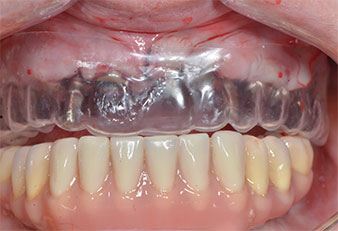

Impianti provvisori

Fig. 8: dopo il fissaggio degli stampi gengivali, gli impianti provvisori sono posizionati nelle posizioni 18, 12, 22 e 28.

Dima in plastica

Fig. 9: una dima in plastica rivela uno spazio sufficiente affinché la protesi esistente possa essere utilizzata come ancoraggio temporaneo sugli impianti provvisori.